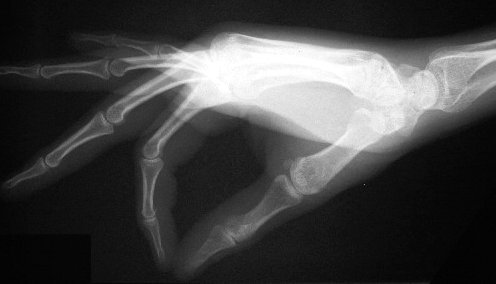

Standard Xray views: Lateral hand

This position is standard, but not ideal. The fingers should be splayed to prevent overlap, as was done for the Xray below.